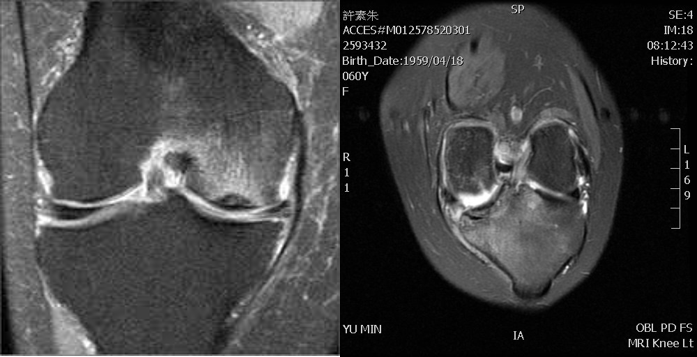

電腦斷層,磁振照影

膝蓋疼痛有時難以定位,X光檢查只對骨頭的部分有較有效的檢查,若是懷疑骨頭的壞死或是韌帶的損傷,還是需要磁振照影的幫助。對於治療或手術的選擇,有時是不可缺少的參考。